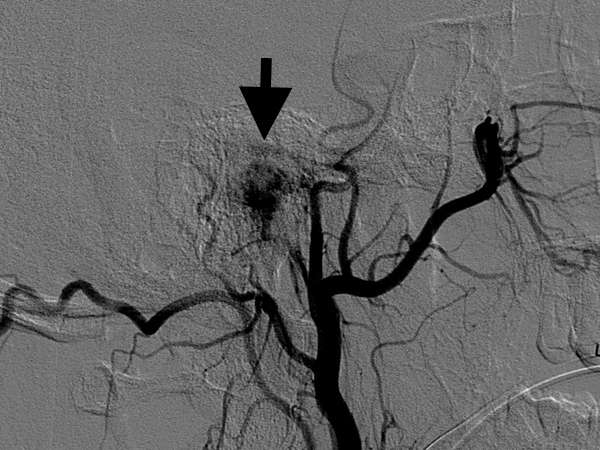

Figure 1: A black arrow indicates a shadow of tumor (Glomus tympanicum tumor). The more blood flow the tumor is supplied, the darker the shadow becomes.